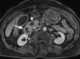

Carcinoma of ampulla

The ampulla of Vater, also known as the hepatopancreatic ampulla or the hepatopancreatic duct, is formed by the union of the pancreatic duct and the common bile duct. The ampulla is specifically located at the major duodenal papilla. [Source: Wikipedia ]